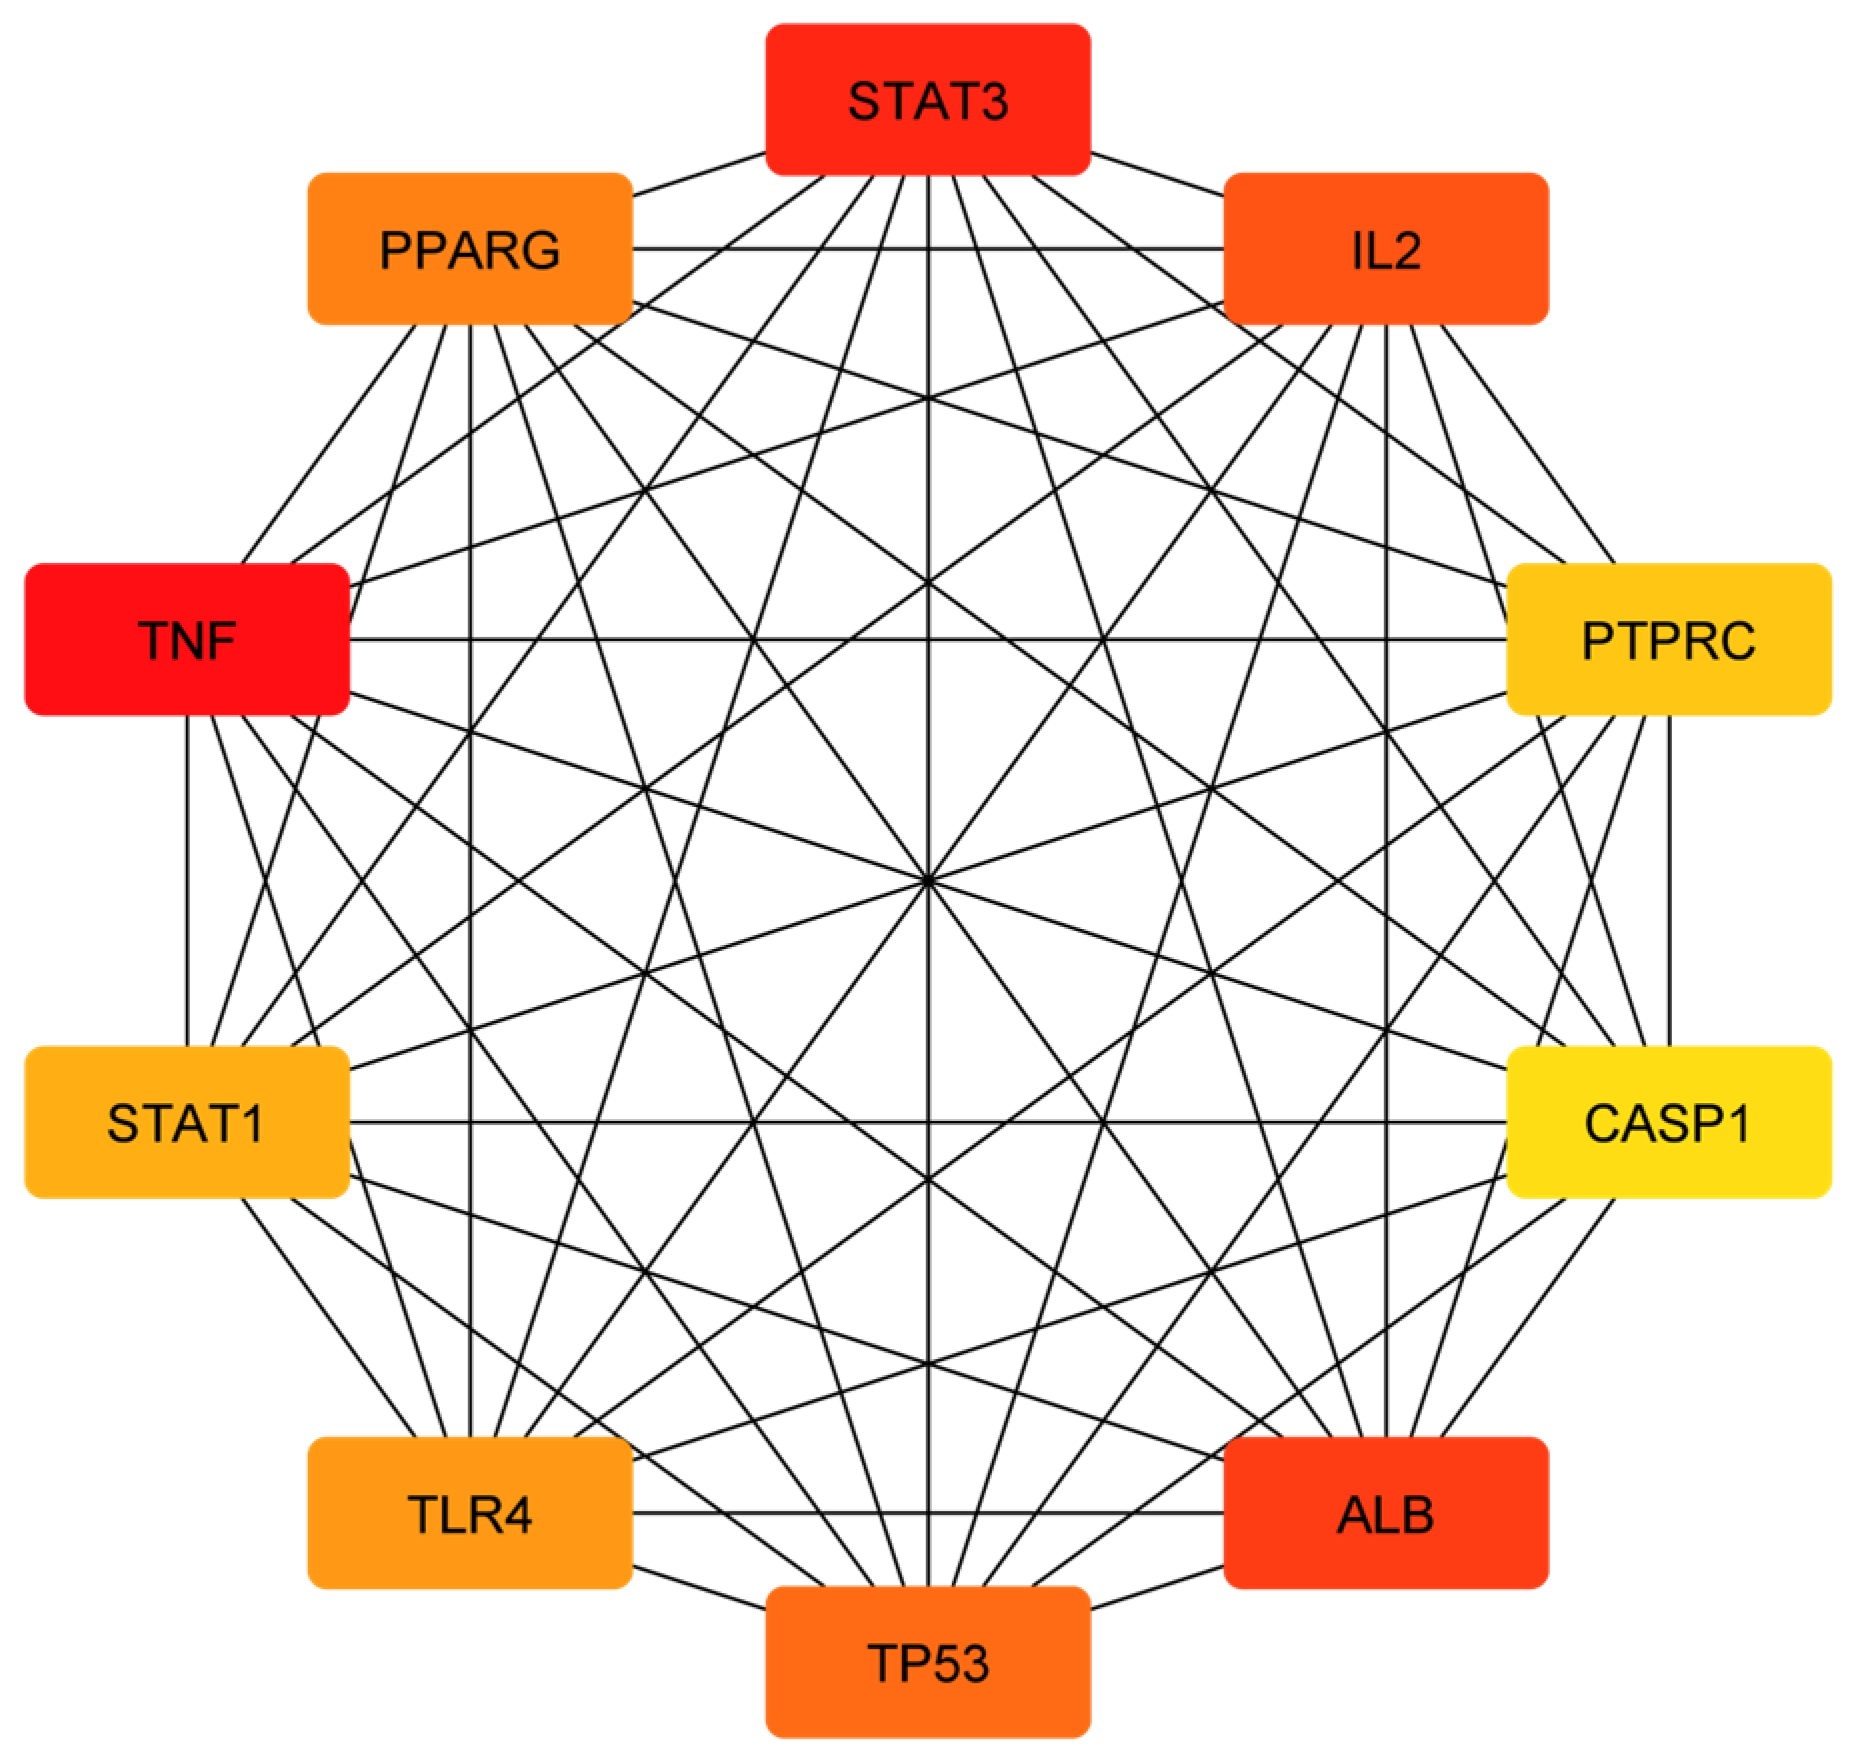

3.2. Compound–Disease Common Target Network Construction and Analysis

3.3. Analysis of Functional and Pathway Enrichment